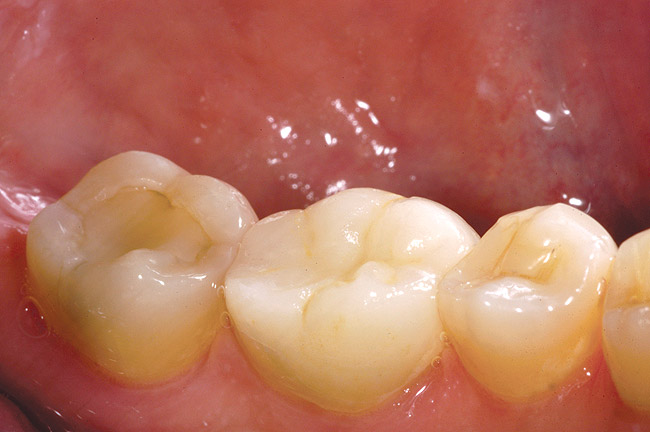

Figure 1c  The final restorations restore and protect the compromised cusps.

Figure 1c

Figure 6c  The final restoration addresses the occlusal, proximal, and lingual compromises of the tooth yet preserves facial tooth structure.

Figure 6c

Figure 7c  Harmonious blending of indirect restorations and natural tooth structure provides improved esthetics and conservation of tooth structure.

Figure 7c